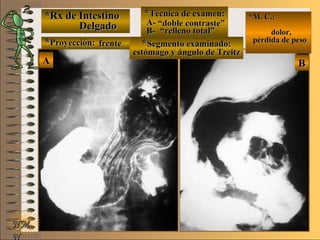

*Rx de Estómago*Rx de Estómago

**Proyección:Proyección:

**Técnica de examen:Técnica de examen:

A-A-

B-B-

C-C-